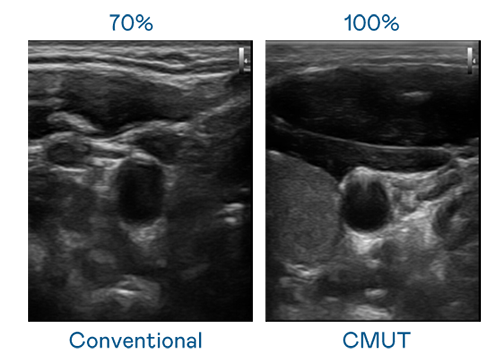

CMUT 技术是一种用电容式微机电元件来产生超音波讯号的技术。与传统 PZT 压电式技术相比,CMUT 频宽增加 30%,更宽频的超音波讯号让影像解析度大幅提升,是实现高影像品质医疗超音波扫描、促进精准医疗发展的关键技术。

大频宽带来超清晰影像

超音波影像的解析度高低,首先取决于探头能发出的讯号频宽。多宝电竞 CMUT 可提供高清晰的超音波讯号,提供高频宽、高灵敏度、影像纹理细节更高的超音波影像,协助医护人员缩短影像判读时间及利用精准的医疗影像进行诊断。